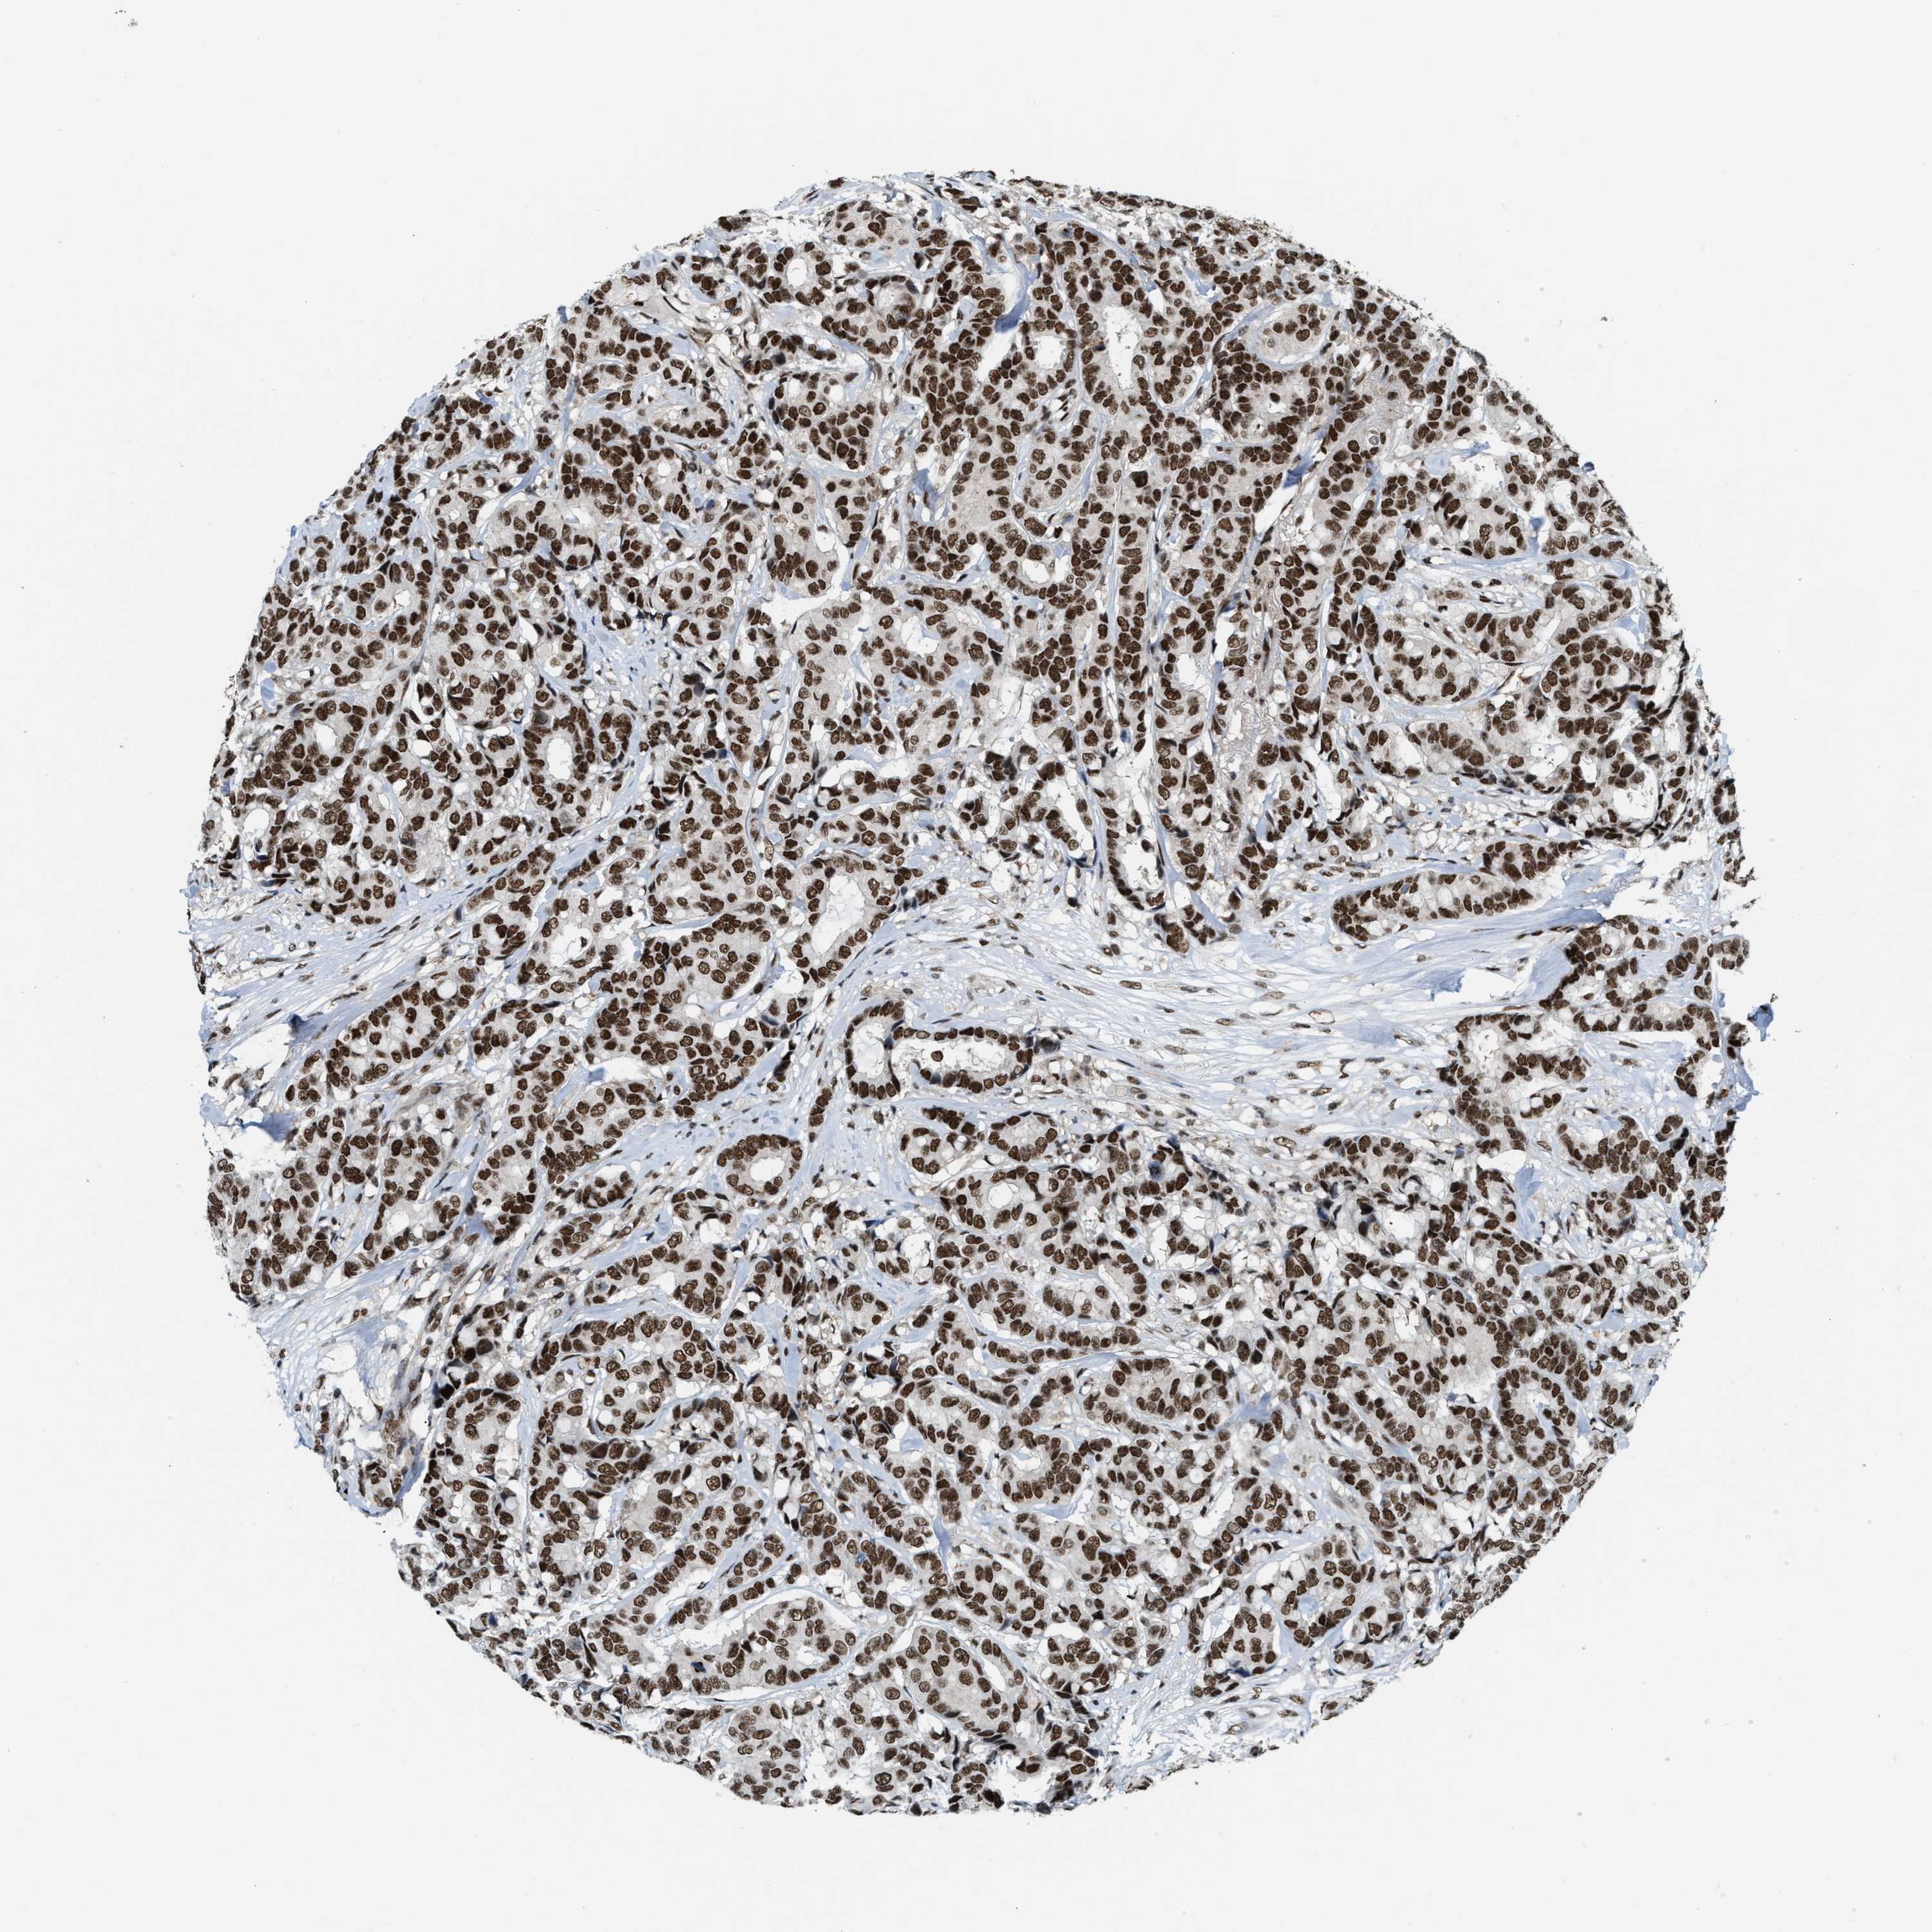

CANCER BREAST CANCER Show tissue menu

BRCA TCGA BRCA VALIDATION PROTEIN EXPRESSION

ANTIBODIES

AND

VALIDATION